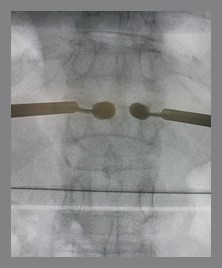

Kyphoplasty is when a balloon is placed in the fractured vertebrae. During this process, bone cement is put inside the space made by the balloon. Two long needles are then inserted through the sides of the spinal column into the fractured vertebra body. These needles guide the surgeon while they carefully drill two holes into the vertebral body. There is a large element of skill involved in this process as the needles and drill holes need to be placed in the correct area. The surgeon then slides a hollow tube with a deflated balloon on the end through each drill hole. Inflating the balloons restores the height of the vertebral body and corrects the kyphosis deformity. Before the procedure is complete, the surgeon injects bone cement through a small hole in the skin (percutaneously) into the hollow space formed by the balloon. This fixes the bone in its corrected size and position.

The drawback, however, is that it is an expensive procedure. The equipment and the balloon can only be used once and the surgeon needs to be a skilled specialized doctor who is trained to carry out this type of procedure. In addition to this, the surgeon uses a fluoroscope to guide a needle into the fractured vertebra body. A fluoroscope is a special X-ray television that allows the surgeon to see a patient’s spine and the needle as it moves. As the fluoroscope is not available in every hospital, this can also be costly for the patient.

1.It is essential to use 2 F-x-ray machines in order to see the picture clearly and quickly – this is much more effective than the old technique that uses only 1 machine.